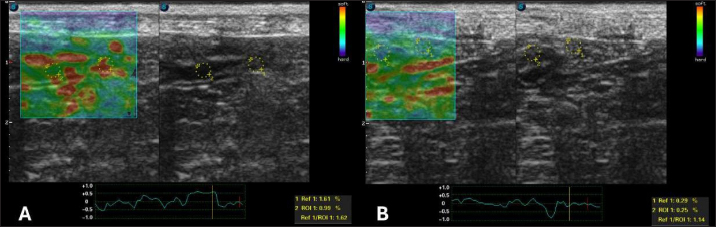

After 30 days of treatment, there were no more laboratory changes (Table 2), the CCECAI was reduced to four (Table 1), and the patient no longer had diarrhea and gained weight. In addition, hyperechogenicity of the intestinal mucosa was reduced, and the values for elastography of the duodenum were as follows: ROI 1 1.61 % and ROI 0.99 %, with an SR of 1.62 (Fig. 5A). In the jejunum, ROI 1 measured 0.29 %, ROI 0.25%, and SR 1.14 (Fig. 5B).

Fig. 5. Semiquantitative elastography of deformation in a cross-section of the intestines of a dog with intestinal lymphangiectasia after 30 days of treatment. The deformation ratio (SR) was obtained by evaluating ROI 1 of the mesentery and ROI 2 of the dorsal portion of the intestinal segment. A duodenum with an SR of 1.62 B-Jejunum with SR=1.14.

In human medicine, the results are similar to those observed in this report. Intestinal inflammation leads to an increase in the hardness rates seen on strain elastography, and after treatment, these parameters are reduced (Gabbiadini et al., 2021). Therefore, they are used for follow-up and as predictors of fibrosis. Despite the similarity, we did not reveal fibrosis in the duodenal mucosa.